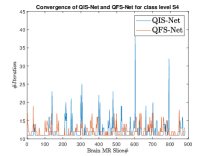

where, represents the true interconnection weight terms of the inter-connection weights as expressed using the Hadamard gate () at an instance (). is a coherent error function of and . Convergence analysis of the proposed qutrit-inspired QFS-Net is provided in Appendix Section -A and demonstrated experimentally with qubit embedded QIS-Net [39] as shown in Figure 3. It can be summarized that the convergence of the QFS-Net is faster than that of the QIS-Net and also follows super-linearity. This claim is also substantiated by the number of iterations required to converge for each image slice in QFS-Net and QIS-Net as illustrated in Figure 4.